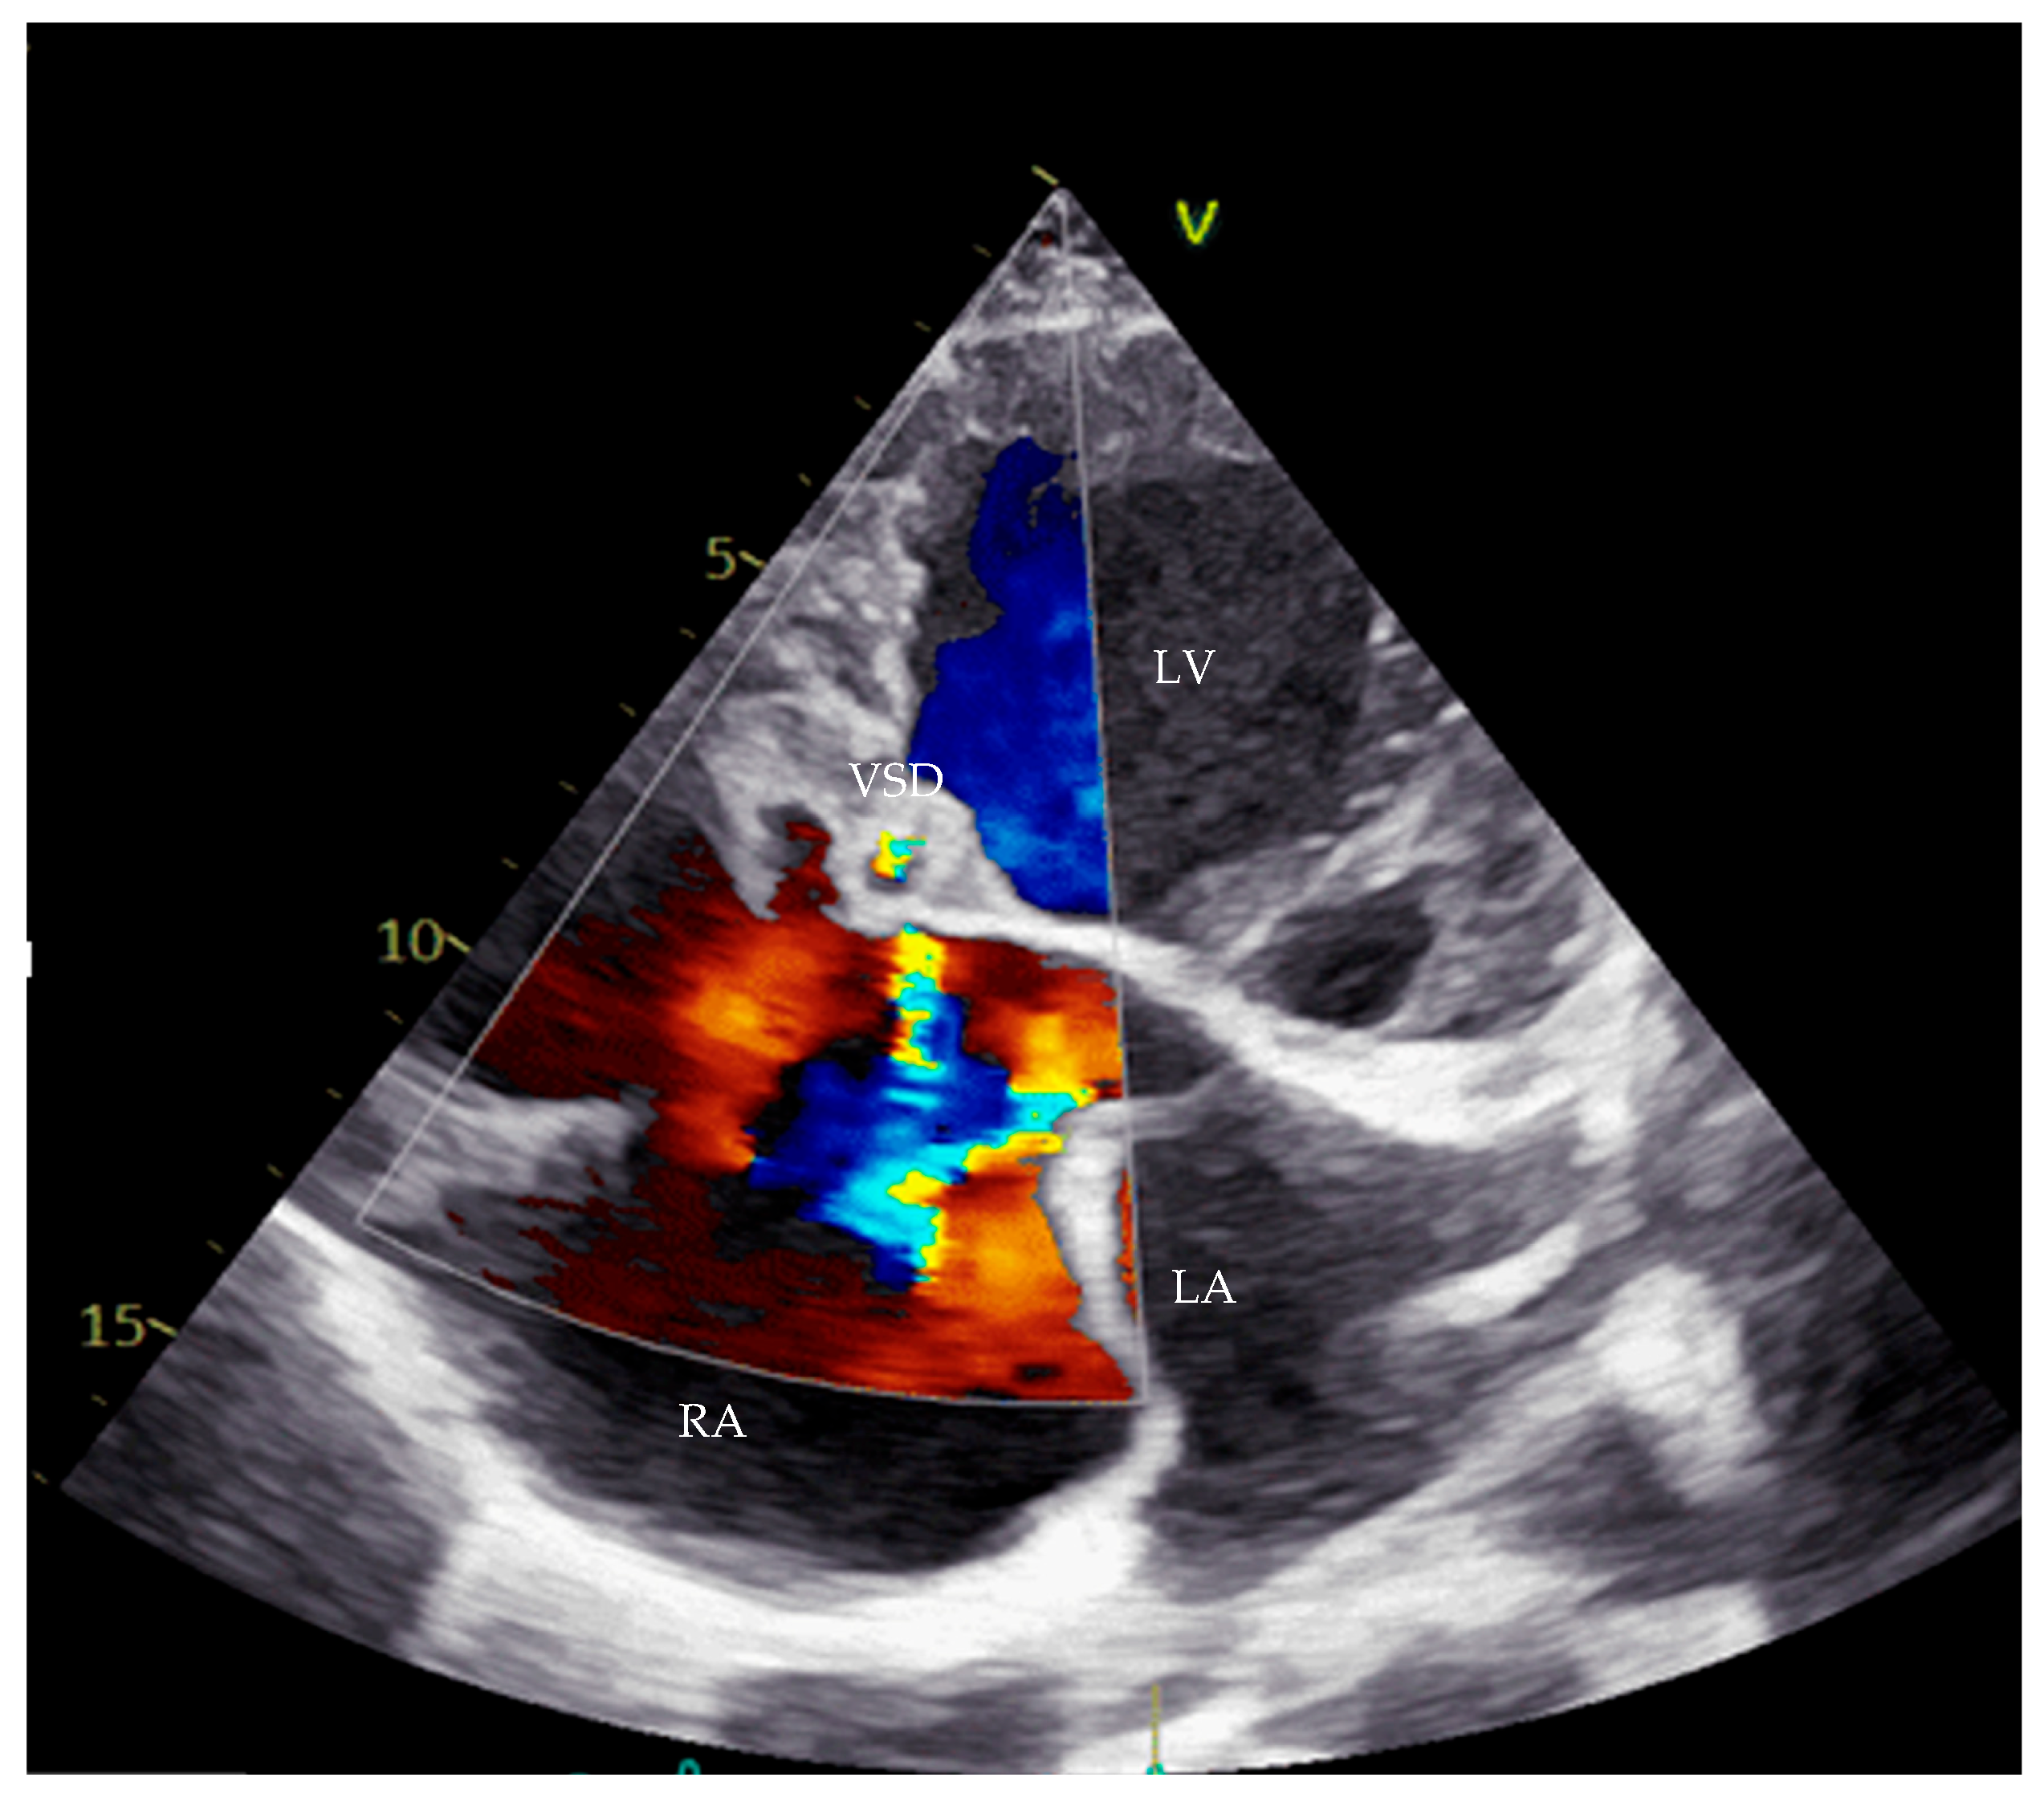

Transthoracic echocardiography (TTE) confirmed the diagnosis of a complete AVCD, with moderate to severe mitral regurgitation (MR) secondary to a cleft in the anterior mitral leaflet, a primum ASD, a ventricular septal defect, RV hypoplasia, and PS. Notably, apical displacement of the septal tricuspid leaflet by 19 mm and the presence of sail-like motion of the anterior tricuspid leaflet were highly suggestive of EA (Figure 1 and Figure 2).

Figure 2. Echocardiography with apical four-chamber view showing VSD Gerbode type. LV—left ventricle, LA—left atrium, RA—right atrium, VSD—ventricular septal defect.